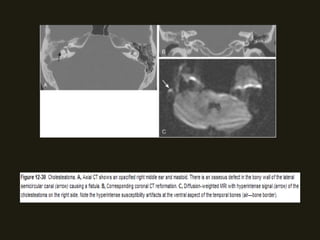

COLESTEATOMA

• TC – formação tecidual no ouvido médio, associada à

destruição óssea (do escudo, dos ossículos e do tegumento

timpânico);

• Difícil diferenciar OMC de colesteatoma na TC;

• RM – não diferencia colesteatoma de outras lesões

• Se colesteatoma > 5 mm – imagens ponderadas de difusão

com sinal hiperintenso;

• Pode ocorrem paralisia facial e erosão do canal facial;

• Raro fístulas para o labirinto, expansão para cápsula óptica ou

fossa craniana média;